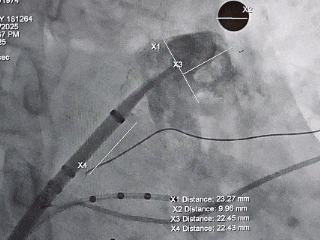

术中DSA肝位造影并测量心耳大小:菜花型左心耳

心耳呈菜花状,远端分叶发达

心耳内无血栓

开口23.27mm,深度22.45mm

本病例为菜花型左心耳,术前造影评估该心耳为多分叶菜花型,远端梳状肌较为发达,开口23.27mm,深度22.45mm,深度足够,建议选择LAFDQ-26封堵器进行封堵。